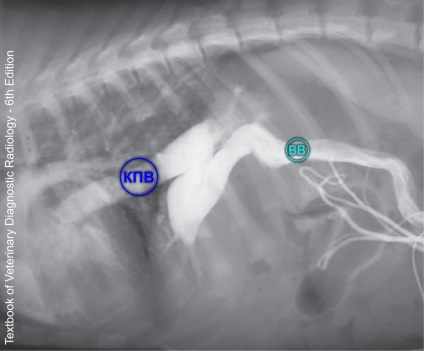

X-sugár kontrasztanyag a mesenterialis vénába - a norma.

Portography bevezetésével radioátlátszatlan anyagnak a vena mesenterica jelenleg a „gold standard” a diagnózis portoszisztémás söntök. Ez invazív módszerrel. Az állat altatásban do laparotomiát végeztünk, kanülált vena mesenterica, kimeneti vonal a katéter külső a has. Továbbá, a törzs injektált kontrasztanyagok, amelyek bélfodri véna belép a portális véna, és azonnal egy sor röntgenfelvételek (fénykép 6). Ez a módszer lehetővé teszi, hogy láthatóvá a vena portae, a sönt (ábra 7), és a máj vérerek.

BB - kapu Bécs.

CPV - caudalis véna Bécsben. BB - kapu Bécs.